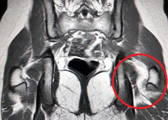

MRI of Ruptured Hip Flexor